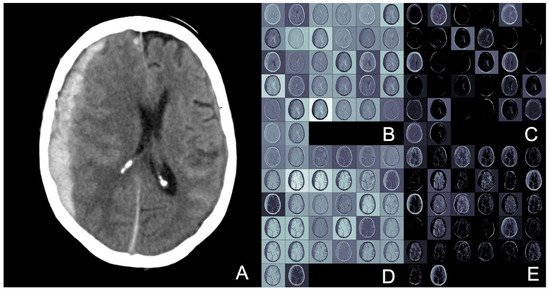

Image Thresholding Improves 3-Dimensional Convolutional Neural Network Diagnosis of Different Acute Brain Hemorrhages on Computed Tomography Scans